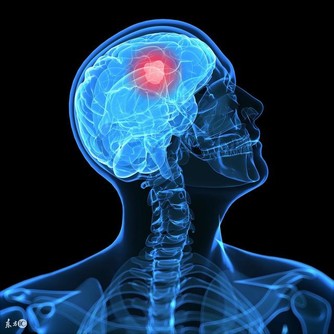

4.防癌抗癌。大蒜中的鍺、硒等,對腫瘤細胞和癌細胞有抑製作用。大蒜中還含有蒜臭素,能夠提高身體免疫力。